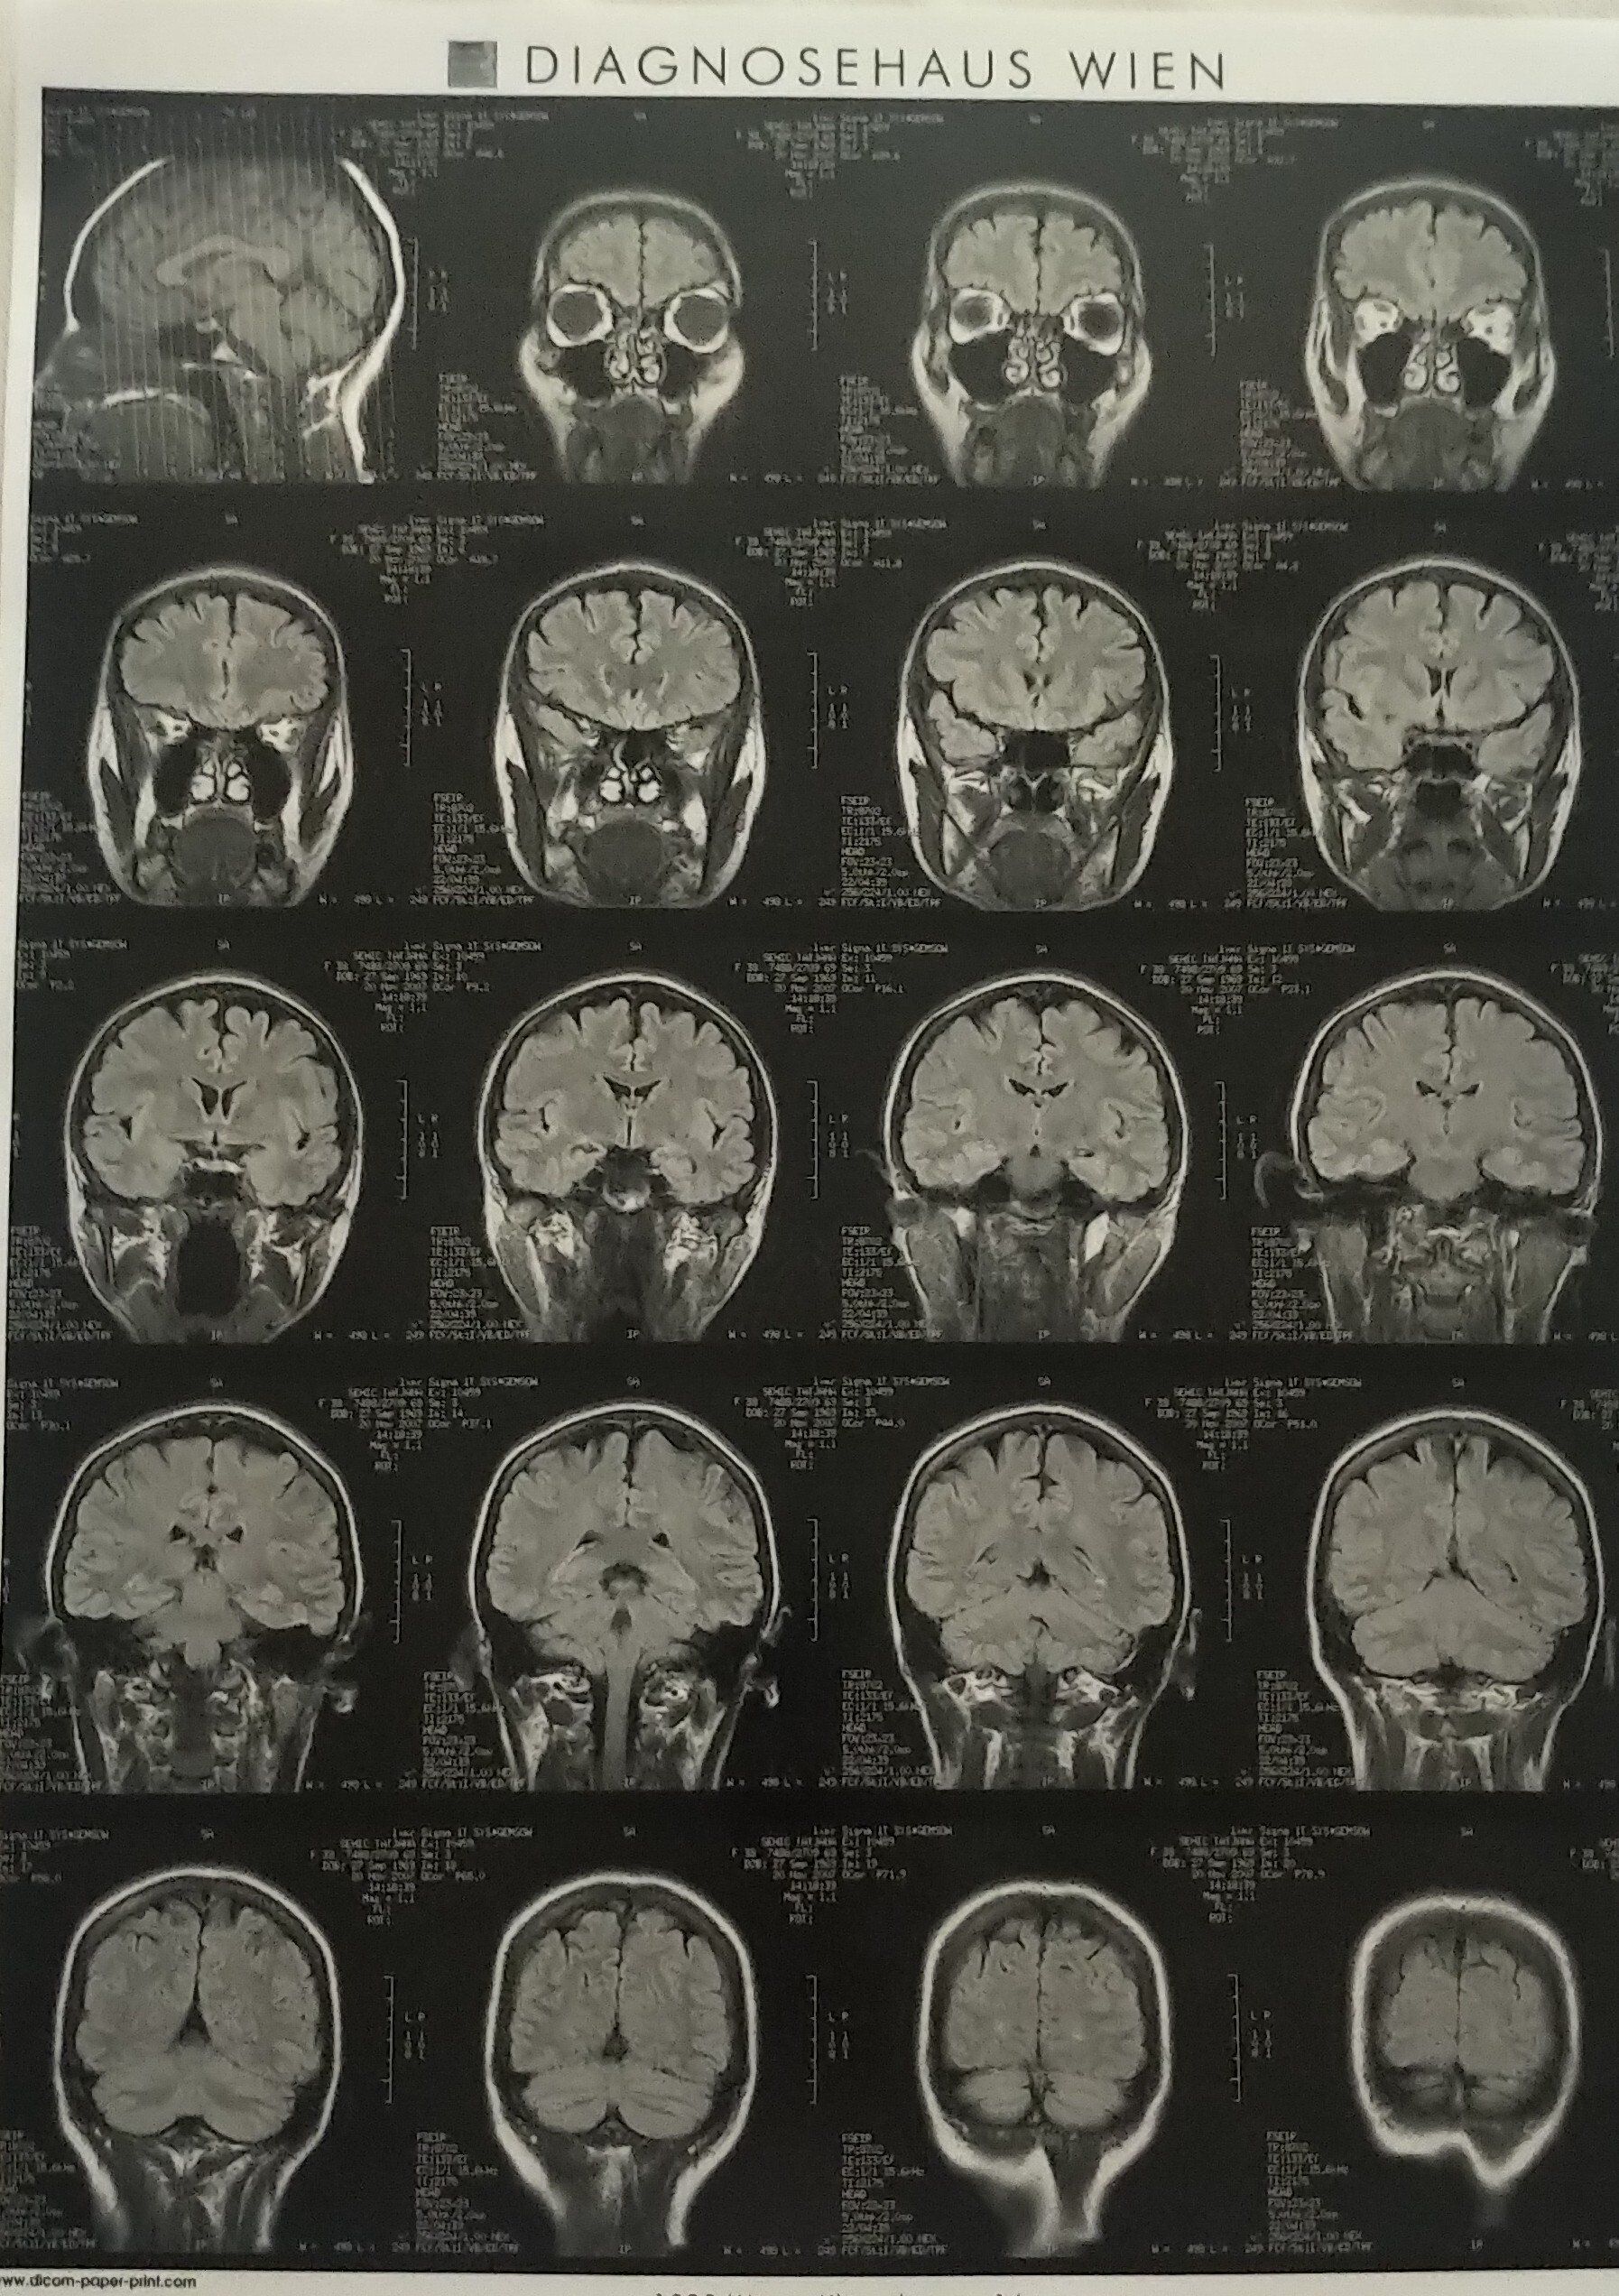

My brain MR- done in stillness, by (secretly) thinking in Croatian, German, English, on

"rain" some years ago, to check tensions in my neck

Corpus callosum consists of about 200 million axons that interconnect the two cerebral hemispheres, known as a left hemisphere and a right hemisphere. The primary function of the Corpus Callosum is to integrate motor, sensory, and cognitive performances between the two cerebral hemispheres (the cerebral cortex ), enabling communication between them.